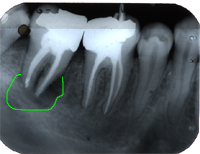

Ein 32 Jahre alter Mann kommt im November 1984 mit Zahnweh am unteren linken, zweithintersten Molaren (Backenzahn) in die Praxis. Das Röntgenbild von Abb. 1 zeigt insuffiziente Wurzelfüllungen bei allen drei Wurzelkanälen und an den Wurzelspitzen sogenannte Granulome, sichtbar als schwarze Flecken (grüne Pfeile in Abb. 1).

In Abb. 2 ist das Röntgenbild 22 Jahre nach korrekter Wurzelbehandlung mit dem nun überkronten Zahn zu sehen. Der Knochen um die Wurzelspitzen ist entzündungsfrei gesund.